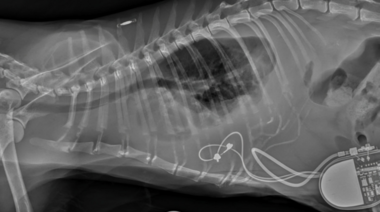

Seguridad en la clínica diaria

Nuevas pautas sobre la colocación segura de sondas de alimentación en perros y gatos

10/02 | Investigadores del Royal Veterinary College desarrollaron criterios radiográficos simples para verificar la posición de las sondas nasoesofágicas y nasogástricas en perros y gatos, con el objetivo de reducir el riesgo de complicaciones potencialmente mortales.